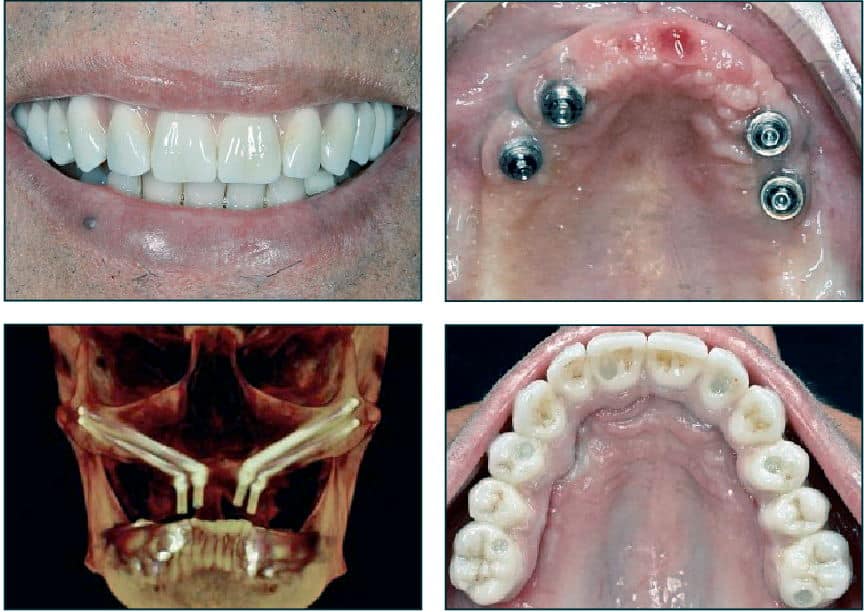

Zygomatic Dental Implants Burbank Dental Implants Dr. Amin

Zygomatic Dental Implants Burbank Dental Implants Dr. Amin Zygomatic Dental Implants Cost Uk Rather than fused to the jawbone, zygomatic implants are attached to the cheekbone when there is not enough bone in the. How much do zygomatic implants cost? However, as dental implants are now more recognised for their durability, insurers are. The dental bridge will be designed and manufactured to create natural. Our prices for zygomatic implants begin at £17,500. Zygomatic. Zygomatic Dental Implants Cost Uk.